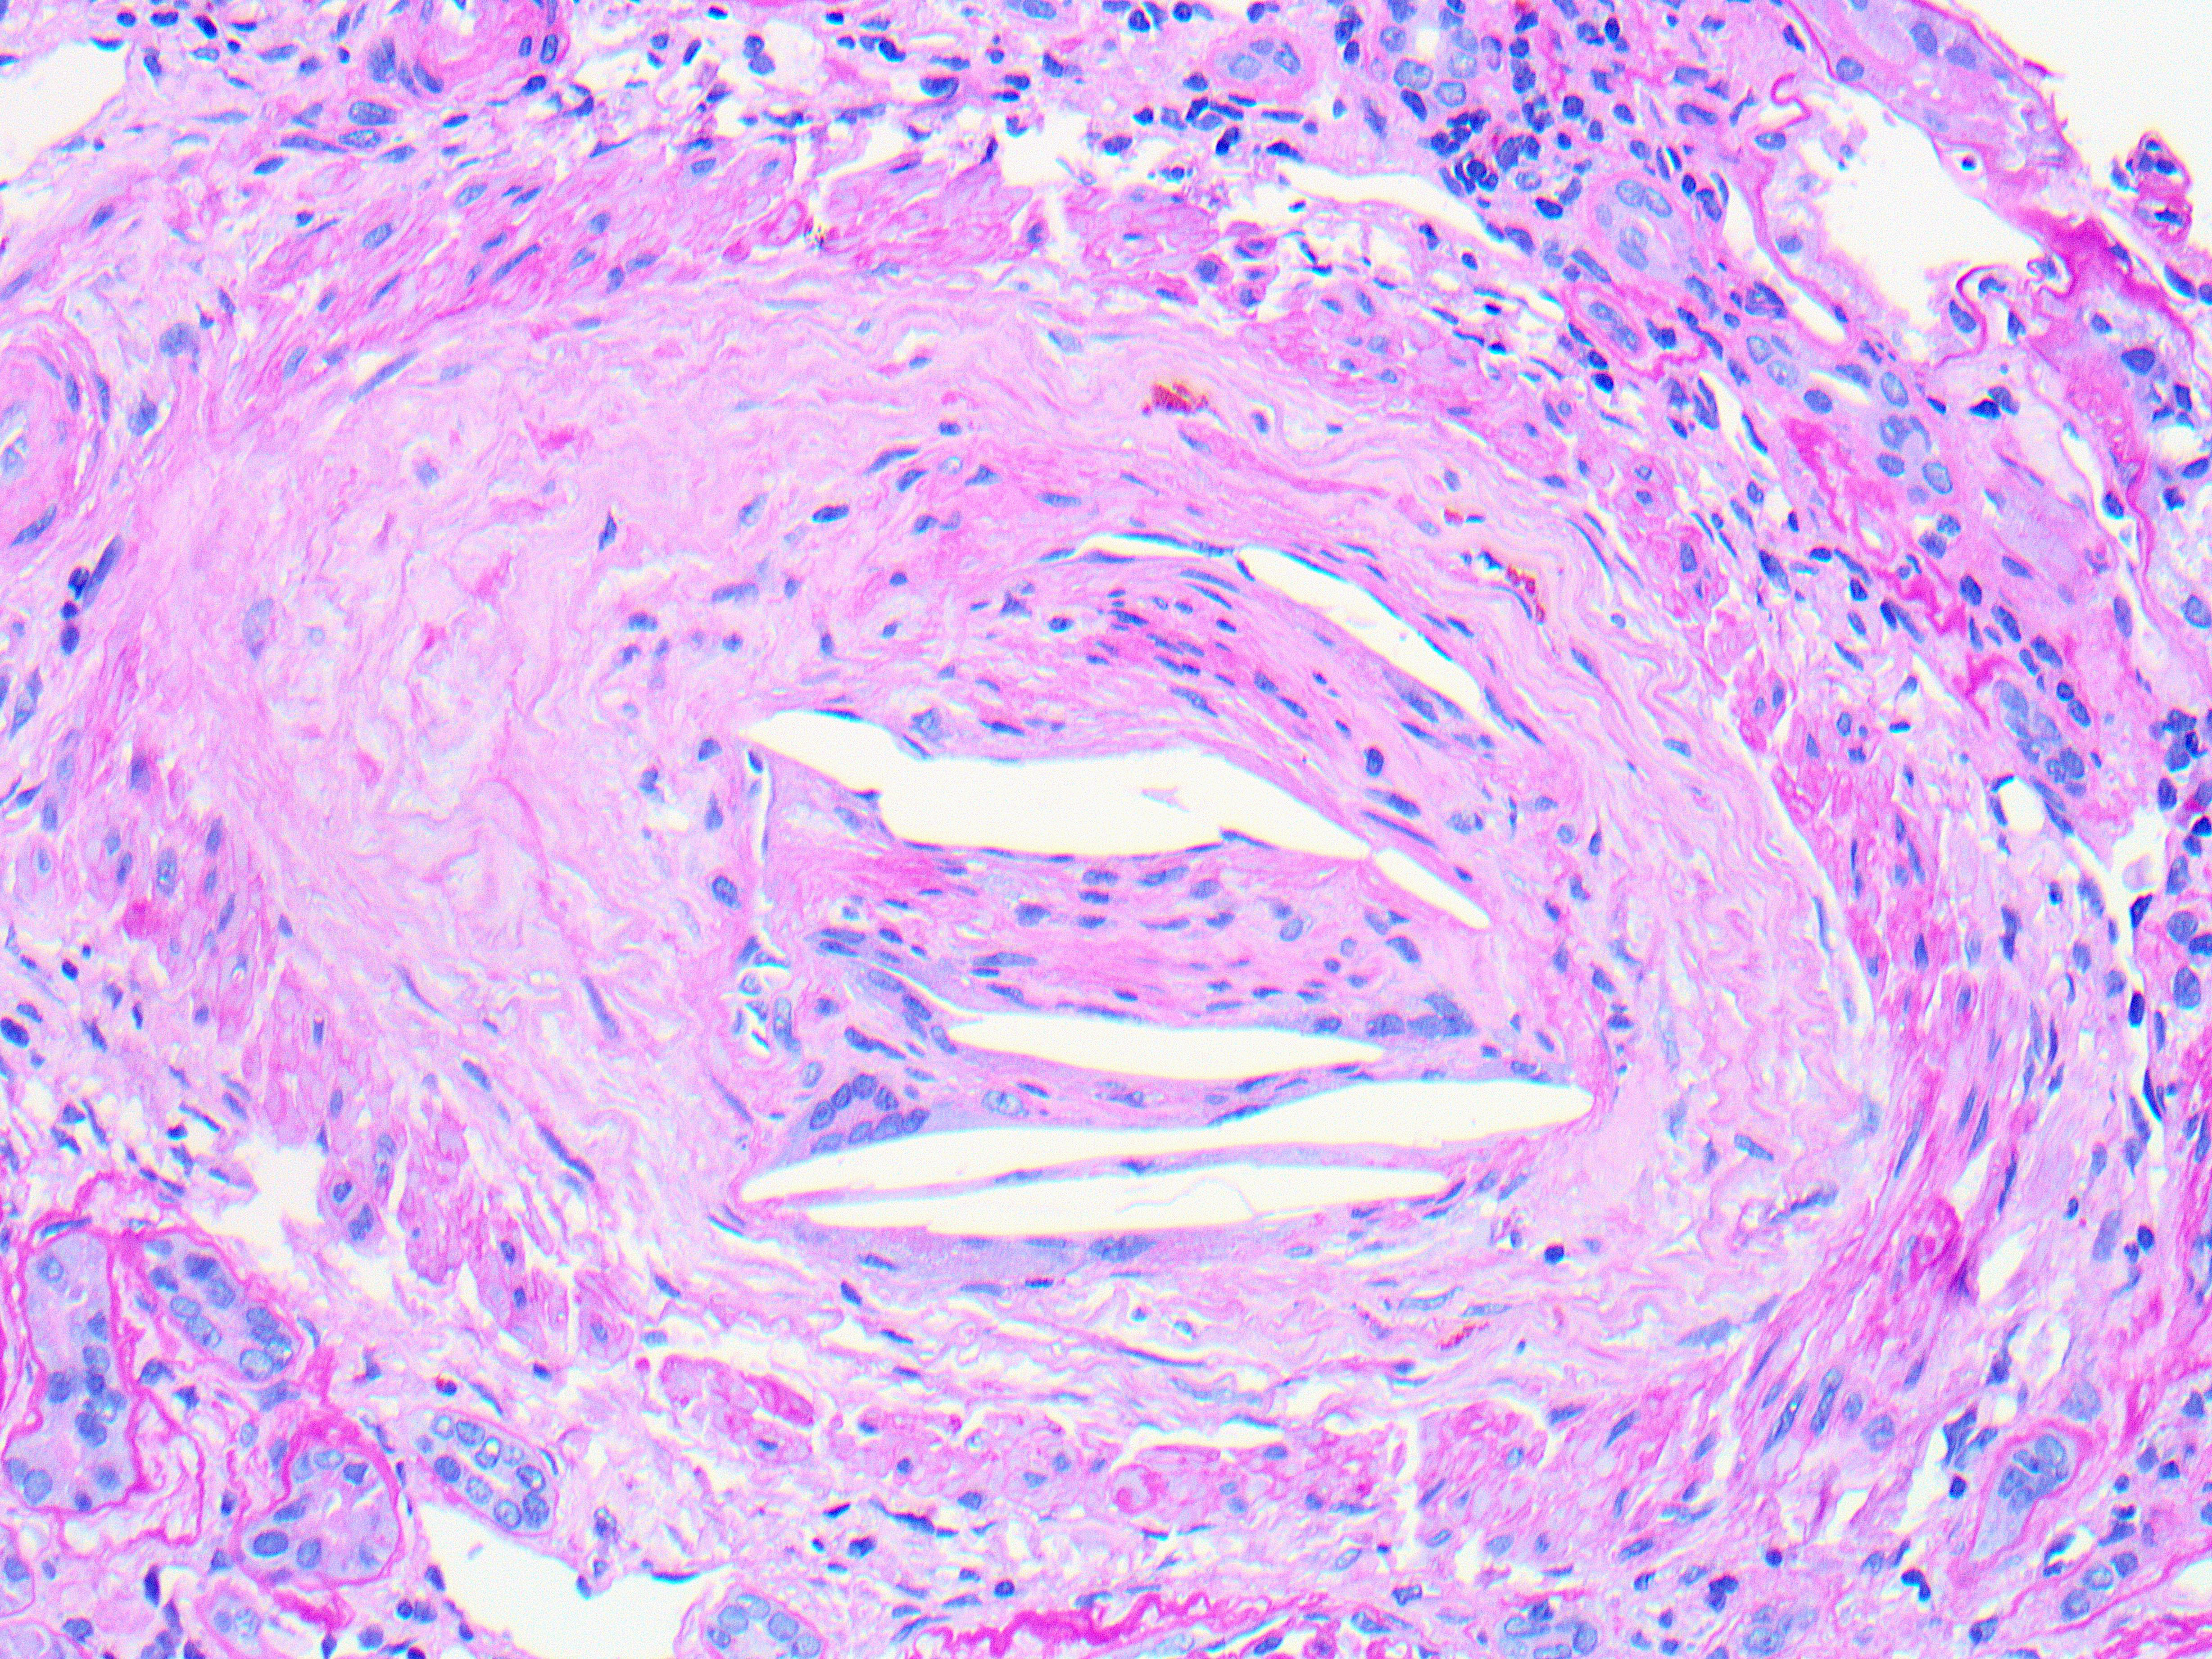

On medium power a cross section of an interlobular artery shows multiple intraluminal cleft-shaped spaces, reflecting the empty spaces left after the dissolution of cholesterol by standard processing (Jones silver Fig a). Chronic ischemic glomerular and tubulointerstitial injury is also evident by focal periglomerular fibrosis and tubulointerstitial scarring, respectively. High power of the same artery shows intimal fibrosis and mild cellular proliferation with occasional mononuclear cells and multinucleated giant cells (arrow) surrounding cleft-like spaces, representing a dissolved cholesterol embolus (PASH Fig b).